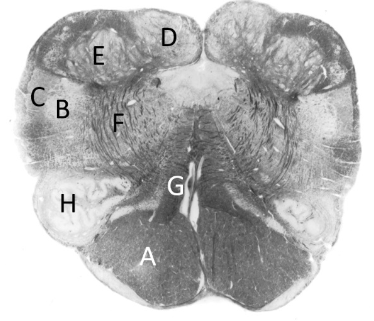

at what level is this?

lower medulla

what is a?

pyramid/ pyramidal tract (lm)

what is b?

spinal trigeminal nucleus (lm)

what is c?

trigeminal tract (lm)

what is d?

nucleus gracilis

what is e?

nucleus cuneatus (LM)

what is f?

internal arcuate fibres

what is g?

medial lemniscus (lm)

what is h?

inferior olivary nucleus (lm)